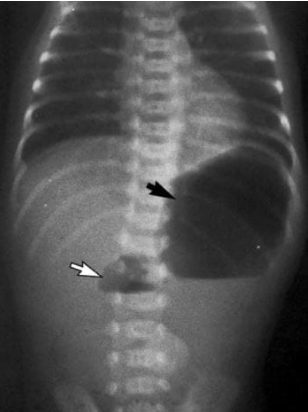

• Ex: sinal de dupla bolha abdominal, que indica atresia dudodenal, indicando que o feto não consegue deglutir o líquido amniótico